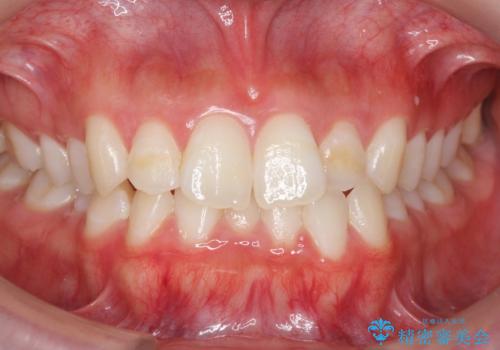

- 前歯のがたつきが気になって来院。

下の歯のがたつきが上よりも多い状態でした。

前歯のがたつきもしっかり治り、喜んでいただけました。